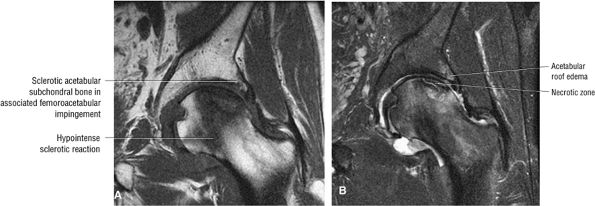

FIGURE 3.86 ● AVN associated with acetabular degenerative changes. Note the hypointense sclerotic reaction of the femoral head. (A) Coronal T1-weighted image. (B) Coronal FS PD FSE image.